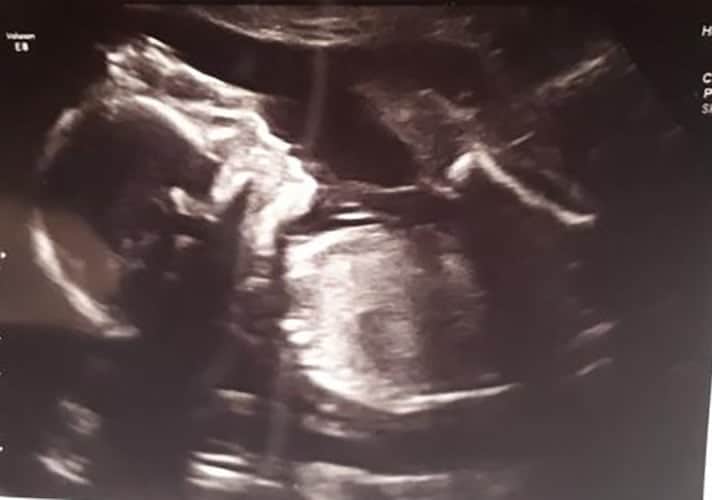

Ultraschallbilder aus dem 2. Trimester (13. bis 28. SSW)

Im 2. Trimester bekommt man oft die schönsten "Ganz-Körper" Ultraschallbilder. Das Baby ist nun so groß, dass man alles gut erkennen kann und noch nicht zu groß, so dass es noch ganz auf das Bild passt. In dieser Zeit lässt sich meist das Geschlecht bestimmen, wobei manche Babys es einfach nicht preis geben wollen und sich immer so drehen, dass man nichts erkennen kann.